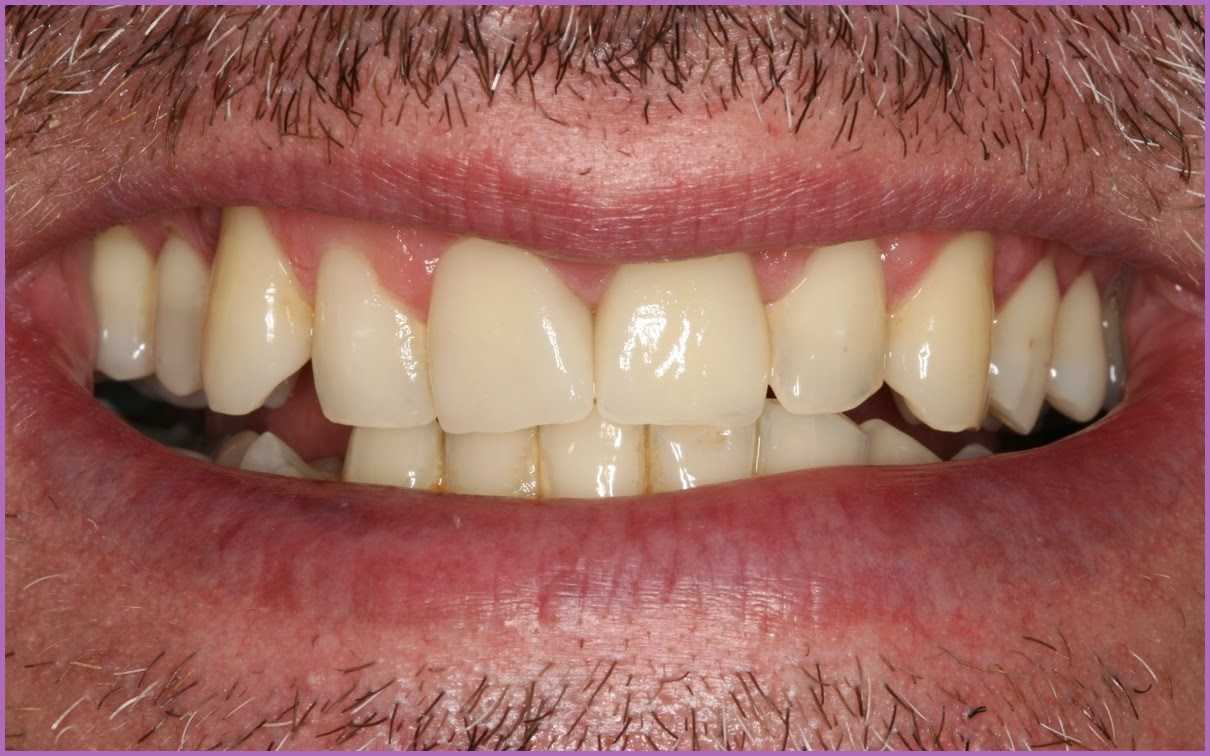

A végeredménnyel nem csak a páciensünk volt elégedett! Az új fogpótlás gyakorlatilag megkülönböztethetetlen a saját fogaktól, és funkcionalitásban is felveszi velük a versenyt.

Páciensünk álmában sem remélte, hogy ilyen szépen rendbe lehet hozni mosolyát. A frontfogaknál minden apró eltérés, hiba azonnal szembetűnik, így ezeknél a kezeléseknél különösen fontos odafigyelni a minőségi munkára és anyagokra.